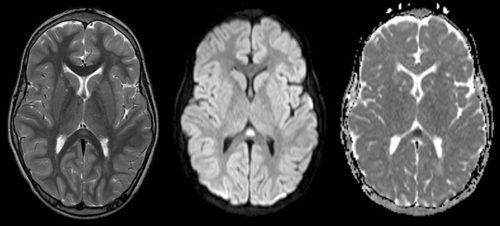

Неизбежным его признаком является гибель мозговых нейронов. Отравление альдегидами вызывает токсическое поражение клеток нервной системы, головного мозга. Некроз отдельных участков ЦНС, полинейропатические симптомы, гибель гепатоцитов, развитие цирроза – закономерное следствие воздействия этанола.

- происходят некротические изменения в головном мозге, закономерным результатом которых и является возникновение энцефалопатии.